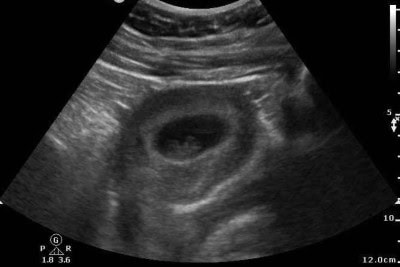

A 28-year-old female presents to urgent care with mild left lower quadrant (LLQ) abdominal pain that began earlier in the day. The discomfort is dull, intermittent, and non-radiating. She denies vaginal bleeding, fever, nausea, vomiting, or urinary symptoms. Her last menstrual period was approximately 2 months ago, although she reports a history of irregular cycles. She appears well and is hemodynamically stable. An abdominal exam reveals mild LLQ tenderness without rebound or guarding. A pelvic …